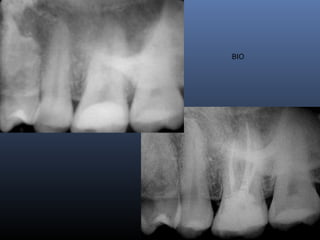

BIO

NECRO